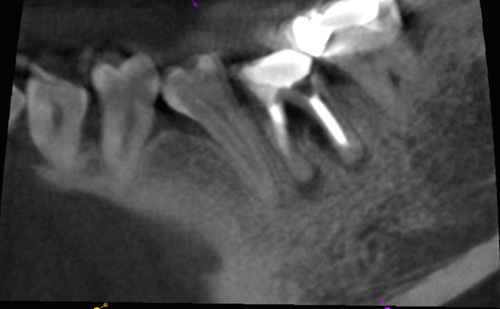

初診時には膿がたまって腫れており痛みもありました。前医では抜歯宣告をされて来院されました。CT画像です。

治療に着手すると近心根(上の画像の左側の根)にはパーフォレーションがあり、遠心根にはヒビが見つかりました。抜歯の選択も説明し、痛みや腫れが取れても長期に安定した状態をキープするのは難しいこともお話ししました。意思決定は患者さんが行います。結果的には歯を残すことを希望されました。

MTAで根充後の画像です。

レントゲンです。コーンカットはお見逃しを(汗)

根尖の病変はまだ残っていますが大分回復方向にあったように見えます。しかしおそらく近心根が割れています。前回の治療でもかなり厳しい状態だったのですからこれをまた再治療する価値はありませんし、私が出来ることはやり尽くしているのでもう一度アプローチしても改善する見込みはありません。したがって私にはこの歯を救う手段は無く抜歯が妥当だとお伝えしました。痛みはそれ程強くは無いので少し考えてみるとのことでした。